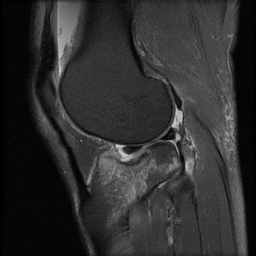

ÀÚ±â°ø¸í°Ë»ç

°æ°ñ ¿ÜÃøºÎ ¾Ð¹Ú°ñÀýÀÌ °üÂûµÊ(»çÁø 8, 9, 10)